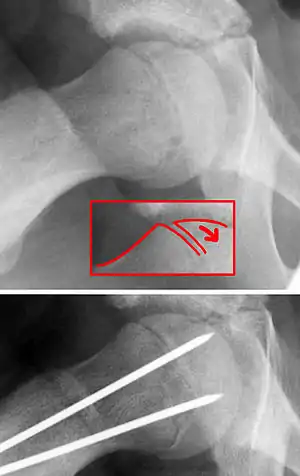

| X-ray showing a slipped capital femoral epiphysis, before and after surgical fixation. | |

The diagnosis requires x-rays of the pelvis, with anteriorposterior (AP) and frog-leg lateral views.[12] The appearance of the head of the femur in relation to the shaft likens that of a "melting ice cream cone", visible with Klein's line. The severity of the disease can be measured using the Southwick angle.

Once SCFE is suspected, the patient should be non-weight bearing and remain on strict bed rest. In severe cases, after enough rest the patient may require physical therapy to regain strength and movement back to the leg. A SCFE is an orthopaedic emergency, as further slippage may result in occlusion of the blood supply and avascular necrosis (risk of 25 percent). Almost all cases require surgery, which usually involves the placement of one or two pins into the femoral head to prevent further slippage.[13] The recommended screw placement is in the center of the epiphysis and perpendicular to the physis.[14] Chances of a slippage occurring in the other hip are 20 percent within 18 months of diagnosis of the first slippage and consequently the opposite unaffected femur may also require pinning.

The risk of reducing this fracture includes the disruption of the blood supply to the bone. It has been shown in the past that attempts to correct the slippage by moving the head back into its correct position can cause the bone to die. Therefore the head of the femur is usually pinned 'as is'. A small incision is made in the outer side of the upper thigh and metal pins are placed through the femoral neck and into the head of the femur. A dressing covers the wound.